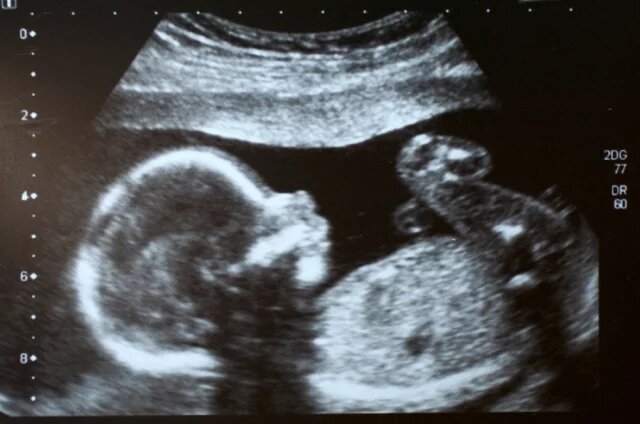

Безопасный метод скрининга позволяет оценить риск хромосомных аномалий у плода.

Начиная с 2026 года беременные в России получили право бесплатно пройти неинвазивный пренатальный тест (НИПТ) по полису обязательного медицинского страхования (ОМС). Это закреплено в обновленной государственной программе гарантий бесплатной медицинской помощи. Что за тест на аномалии ребенка можно сдать по ОМС — читайте в справке aif.ru.

Это современный и безопасный метод скрининга, который позволяет оценить риск хромосомных аномалий у плода. С его помощью можно выявить синдромы Дауна, Эдвардса, Патау, нарушения в количестве половых хромосом и некоторые другие генетические патологии. Главное преимущество — неинвазивность: для анализа достаточно взять кровь из вены будущей мамы, что исключает риски, связанные с инвазивными процедурами, такими как прокол для забора околоплодных вод.

Бесплатный НИПТ по ОМС предназначен для беременных, у которых по результатам традиционного скрининга первого триместра выявлен средний или высокий риск хромосомных аномалий у плода. Тест можно проводить с 10-й недели беременности. Ранее такая диагностика была преимущественно платной, стоимость могла достигать 50 тысяч рублей.